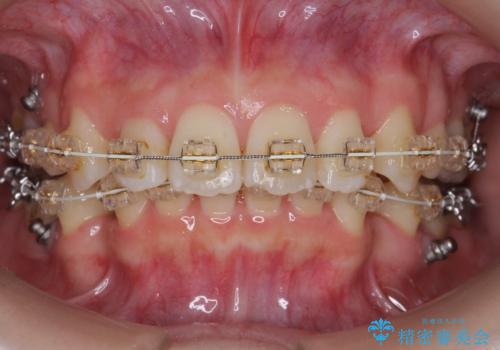

矯正治療をおすすめし、ちょうど虫歯がひどい歯は抜歯して前歯を下げました。

下顎の大臼歯が前に倒れこんでいたため、矯正用ミニスクリューで後ろに起こしています。

治療の難易度としてはかなり高めでしたが、無事終了することができました。